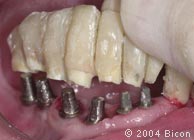

3. |

病人原有义齿的唇颊侧观。 |